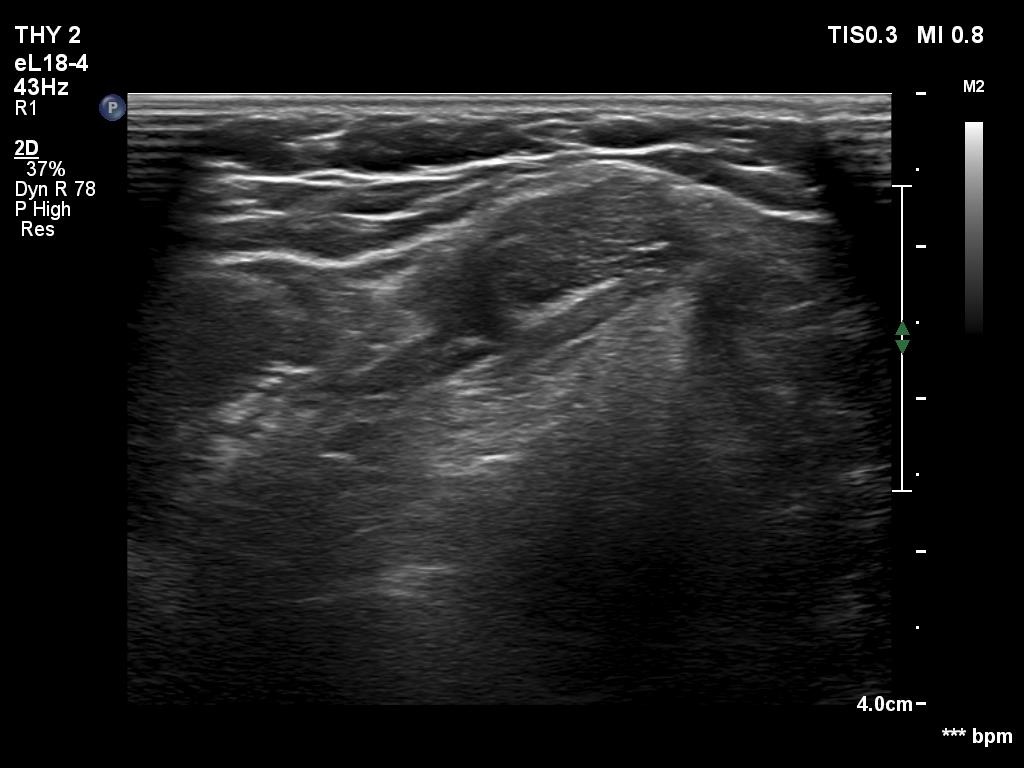

One year after the surgery (second row of images):

Clinical data: On routine follow-up, the surgeon palpated a mass in the middle of the neck. The patient was referred for evaluation and cytology of the mass.

Palpation: a not firm mass in the middle of the neck above the level of the thyroid.

Laboratory tests: TSH 3.01 mIU/L on daily 75 microgram levothyroxine.

Ultrasonography. Connective tissue replaced the thyroid. Approximately 4 cm above the level of the thyroid, a hypoechoic mass was found. The echo structure was identical to the that of the thyroid seen before the surgery.

Cytology was performed form the mass and resulted in benign hormonal atypia. Wash-out thyroglobulin exceeded 10,000 pg/mL.

Comment. The palpation remains a crucial examination in thyroid patients. If we did not palpate the neck, this lesion would be very likely overlooked on ultrasonography because of the similarity of the echo structure to the neighboring muscle tissue. The two types of tissue differed in two things, the thyroid gland contained less thick and shiny connective tissue bundles, and circulation was detected in it.